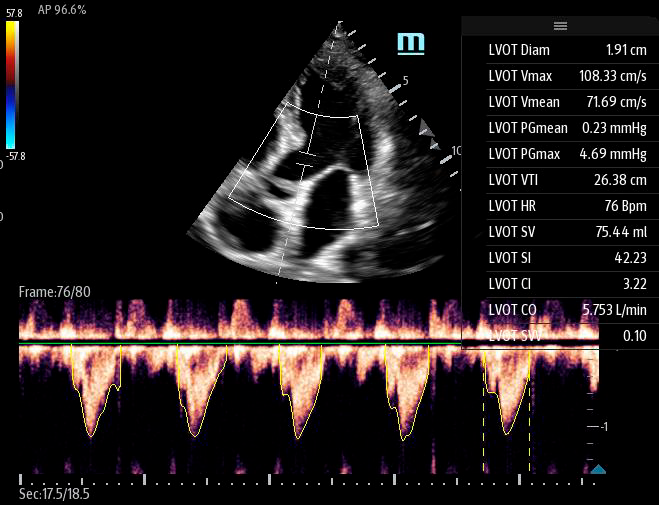

Чтобы использовать уравнение, нужно получить поток выносящего тракта левого желудочка в PW допплере — это достаточно кропотливая работа. В ультразвуковых системах Mindray Resona i9 эта задача решается автоматической оценкой потока выносящего тракта – Smart VTI.

Доктору остается получить 5-ти камерное сечение сердца и нажать одну кнопку на сенсорном экране. Прибор сам выберет расположение контрольного объема, получит спектрограмму и обведет спектр с расчётом всех показателей. Быстро и эффективно.